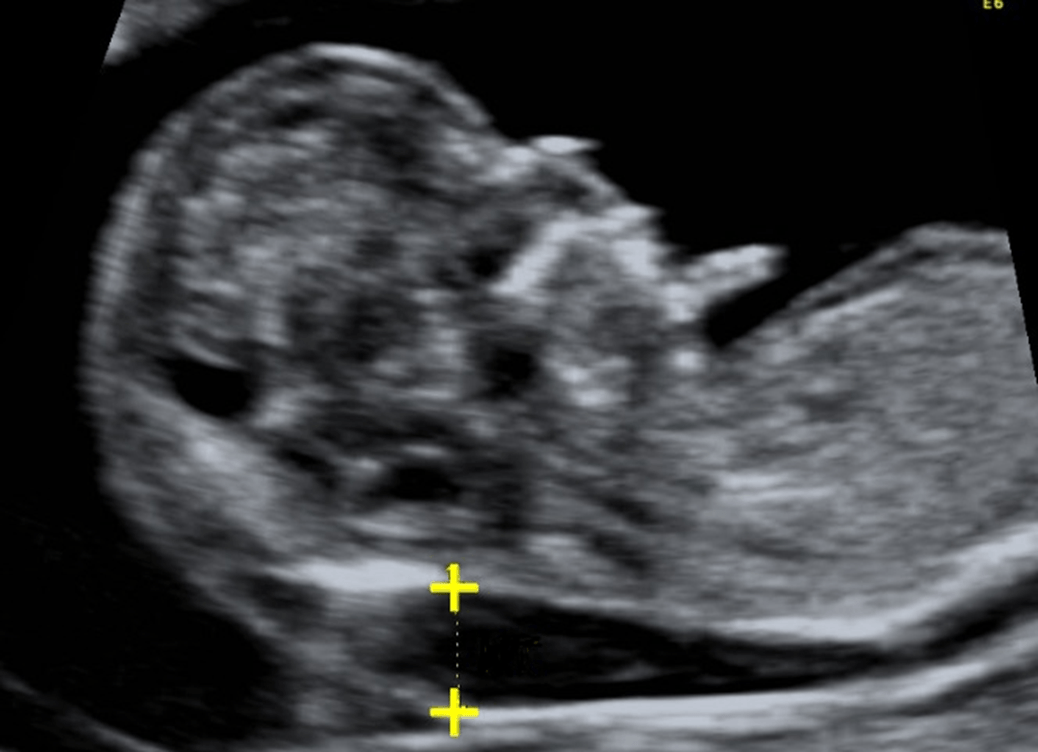

A fetal anatomy scan is shown below.

Name 2 common diagnoses associated with this finding.

What is increased nuchal translucency?

What are Trisomy 21, also 18 and 13, Turner syndrome, Triploidy?